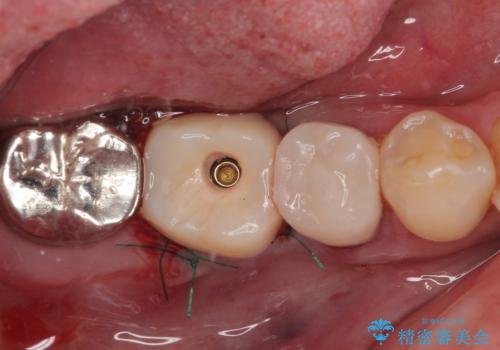

インプラント埋入時に十分な安定値を得ることができたため、速やかに仮歯を装着し、最小限の通院回数で治療を終えることができました。

- むし歯を放置したままで、インプラント治療を希望して来院された患者様です。

左右ともにインプラントが必要な状態でした。